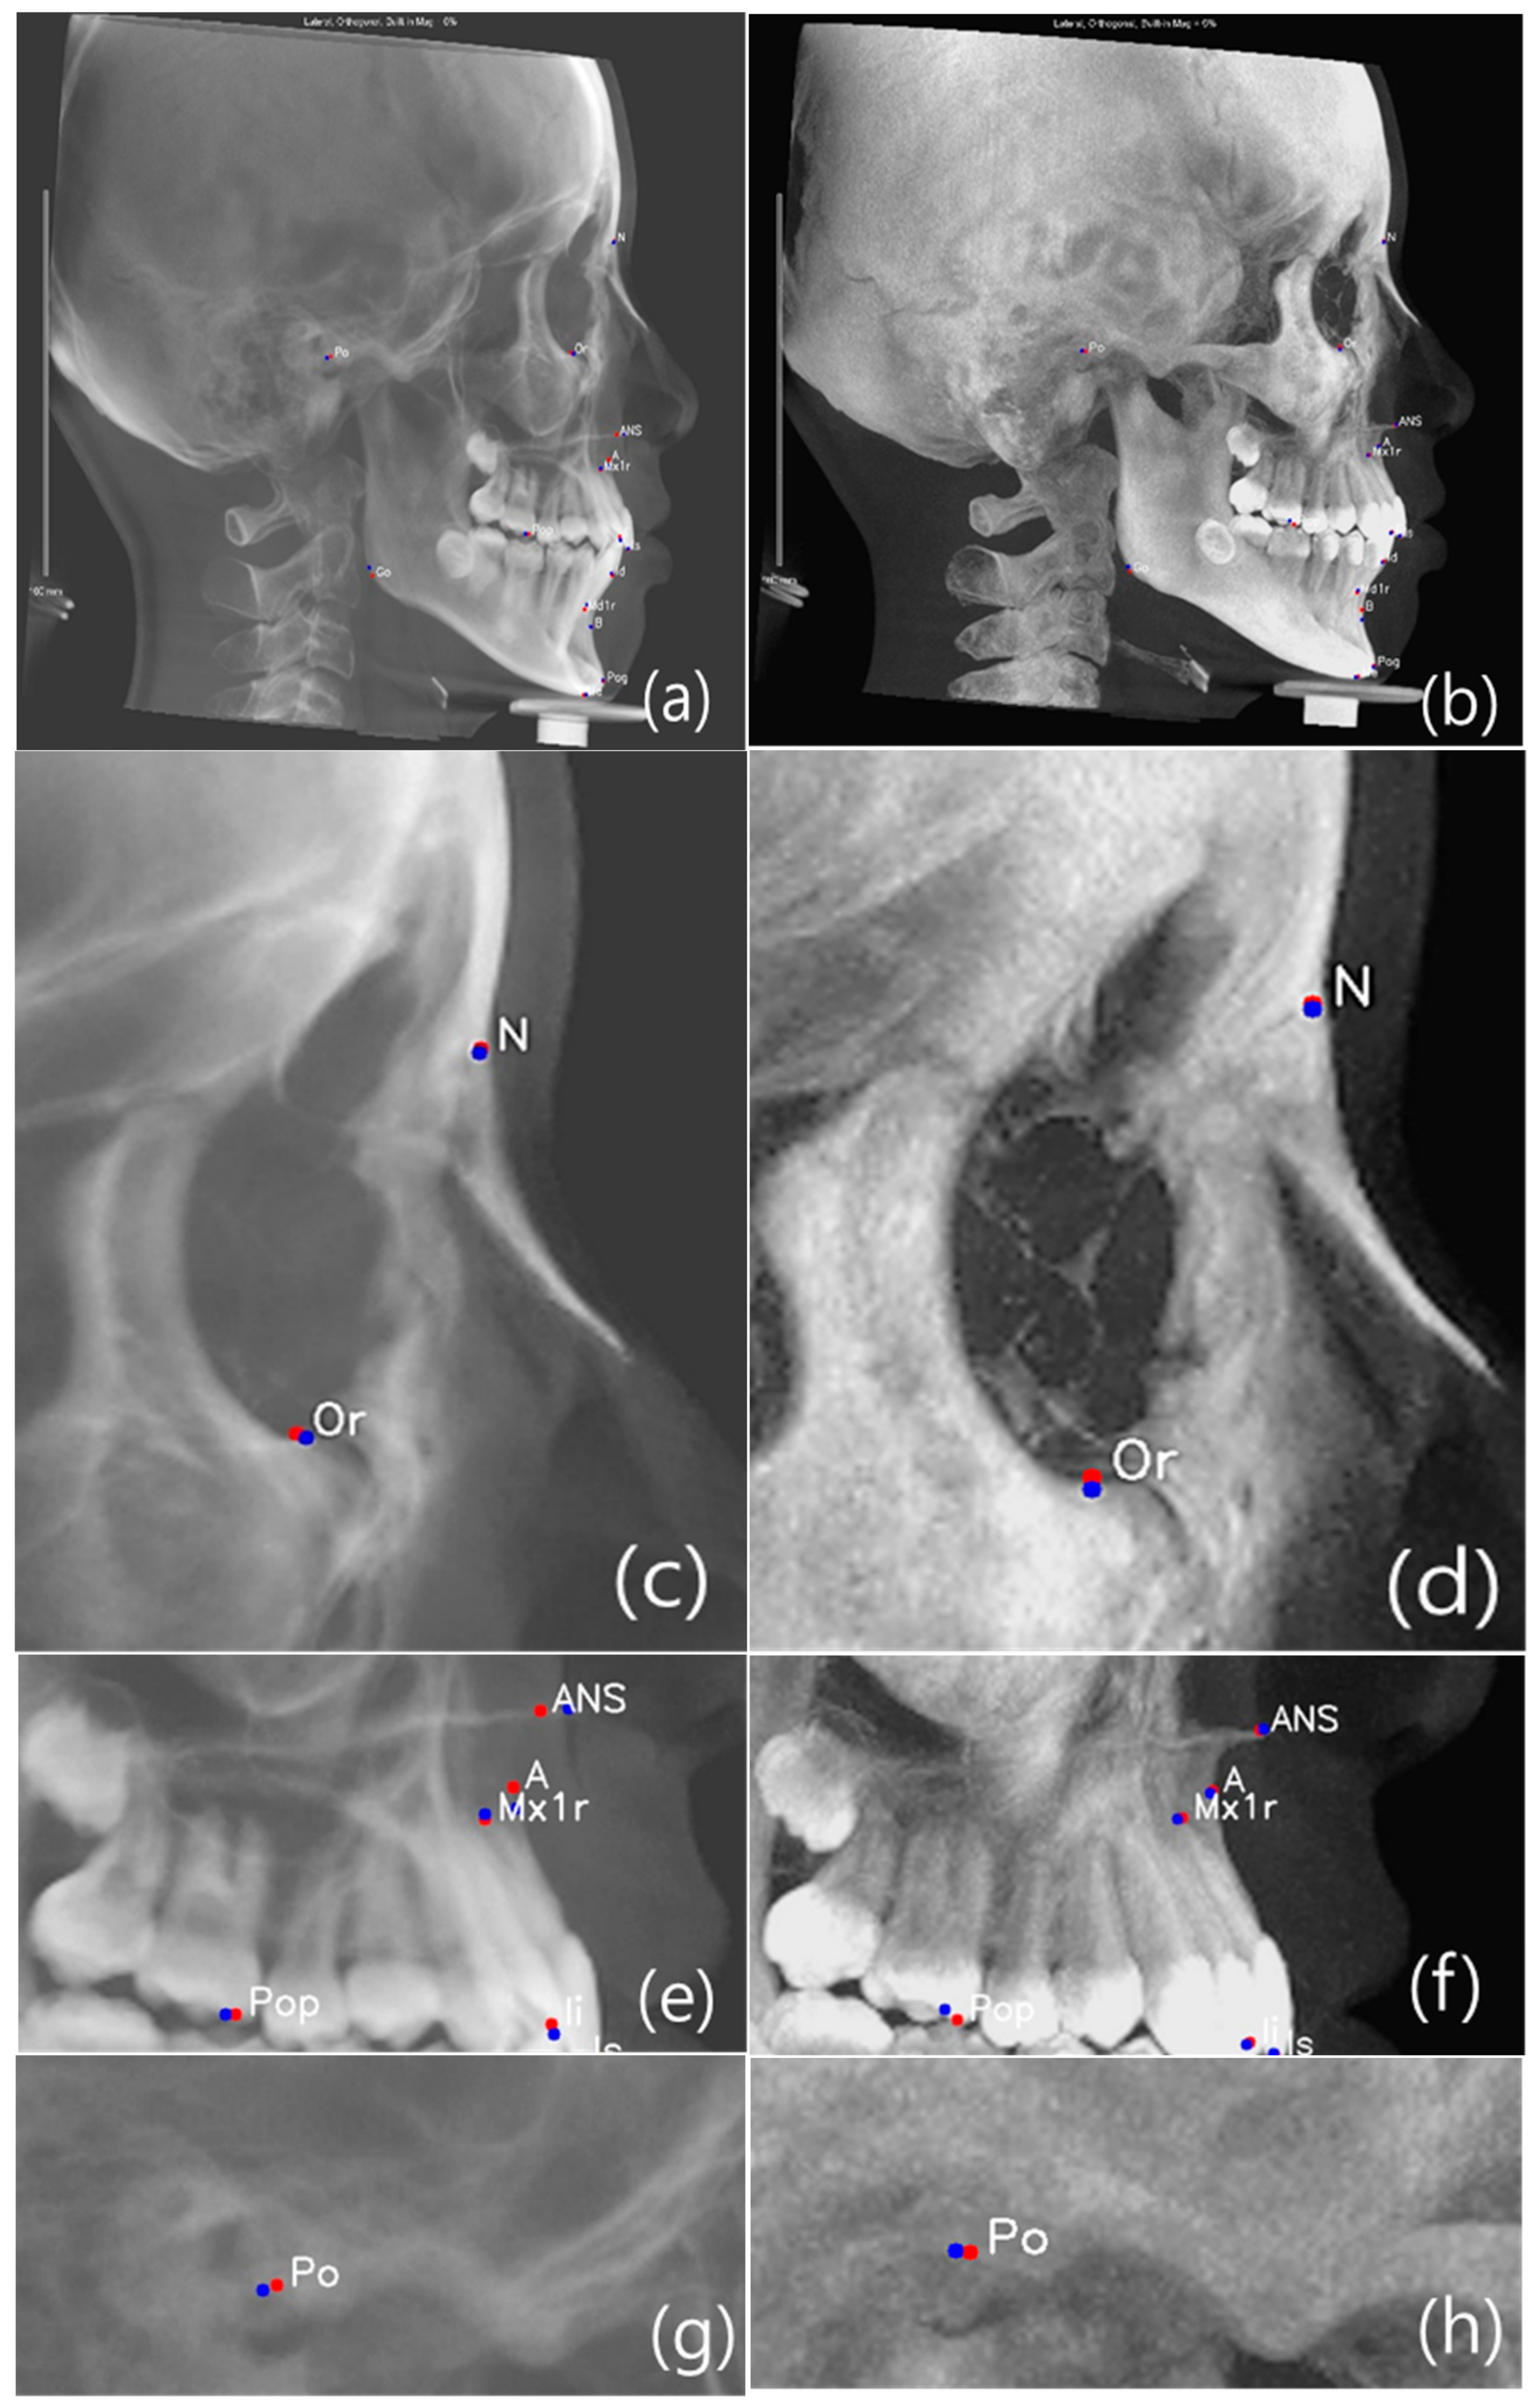

Previous studies compared reproducibility between conventional lateral cephalogram and different types of CBCT synthesized 2D lateral cephalograms (MIP, Ray-sum or usual). Conclusion of these studies was that linear and angular measurement derived from CBCT synthesized cephalogram resulted in higher consistency than conventional cephalogram [1,2,6,40,41]. We used CBCT synthesized combination data to perform efficient landmark identification for training. We used 15 landmarks positioned on the anatomic structure contours that were displayed more clearly in the MIP image. Comparison of AI prediction results between CBCT-LC and MIP-LC are shown in Figure 5.

Figure 5.

Comparison of AI prediction between CBCT-LC (a,c,e,g,i) and MIP-LC (b,d,f,h,j); Orbitale c and d; Maxilla e and f; Porion g and h; and Mandible i and j. The red dot is manual identification (truth ground), and the blue dot is AI prediction.